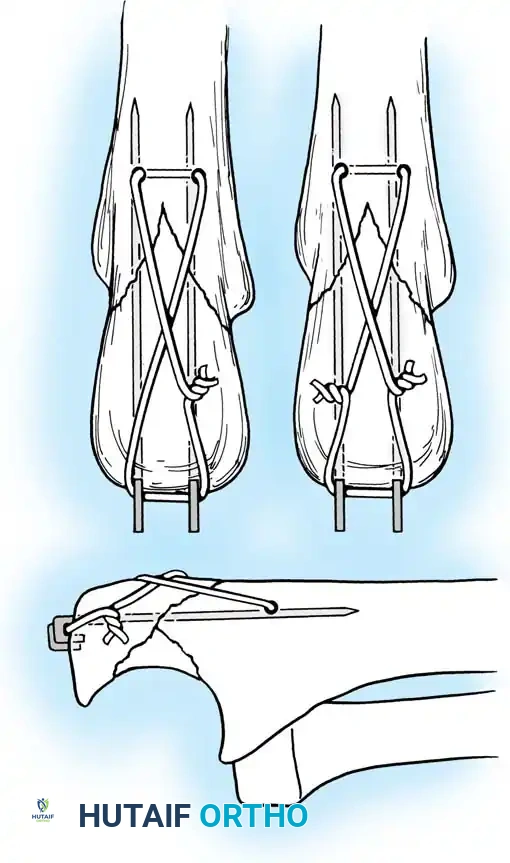

Fig. 54-53 A and B, Simple loop is not as satisfactory as figure-of-eight loop for fixing fracture of olecranon. C, Simple loop is insufficient when its long axis is in or anterior to long axis of olecranon.

Fig. 54-54 Internal fixation of olecranon with tension band wire loop. Wire passed through hole drilled in distal fragment and through triceps aponeurosis adjacent to bone. Figure-of-eight loop adds stability to fracture and prevents distraction and posterior bowing.

Fig. 54-56 A and B, Transverse olecranon fracture repaired with Kirschner wires and tension band technique. C, Double twist modification of wiring suggested by Weber and Vasey.